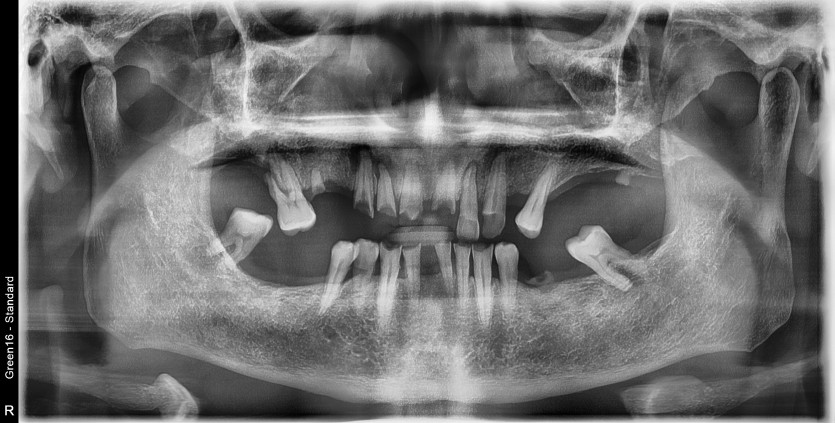

만 66세 전체 임플란트 증례(하악 일부)

전체 임플란트 증례입니다. (하악 일부)

16개의 임플란트로 완성하였습니다.